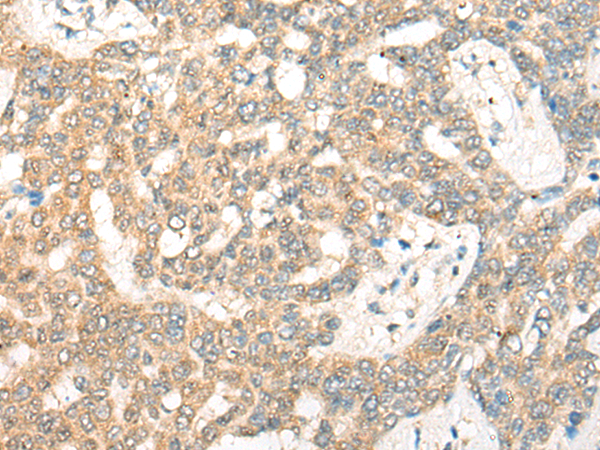

分类: 科研抗体货号: P13188别名: GES; GD:REM应用: IHC反应种属: Human